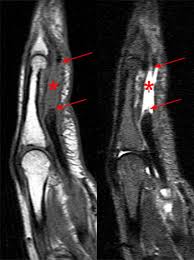

The fds tendon divides into two slips that wrap around the fdp to insert into the sides of the middle phalanx. When a muscle contracts, the tendon pulls on the bone causing the joint to move. Note the joining of the two slips (arrows) before their final individual insertions. The flexor digitorum profundus is a muscle in the forearm of humans that flexes the fingers (also known as digits). This region includes the distal part of the fdp tendon.

Terminology usually accepted recognizes 6 arcifom pulleys (a0 to a5) and 3 cruciform pulleys (c1 to c3). Note the joining of the two slips (arrows) before their final individual insertions. The tendons of the fdp and fds lie deep in the palm of the hand, beneath the superficial palmar arch and the superficial branches of the median and ulnar nerve. Flexor digitorum superficialis (fds) and flexor digitorum profundus (fdp). The largest compartment is the carpal tunnel. Anatomy of the flexor tendons. Damage to the foot and ankle tendons are a common cause of foot pain, typically caused by overuse, overstretching or an injury. Flexor digitorum superficial splits into radial and ulnar slips prior to insertion on middle phalanx. Zone 1 is distal to the flexor digitorum superficialis insertion (fds) and contains only the flexor digitorum profundus (fdp), zone 2 contains both the. This region includes the distal part of the fdp tendon. As with tendons elsewhere, the extensor tendons are best assessed in the axial plane. The fds tendons are the most palmar, and the fds tendons to the long and ring fingers are most superficial. Flexor digitorum profundus muscle is a powerful flexor of the fingers.